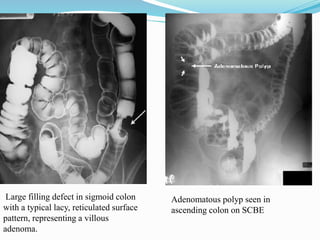

This document discusses colorectal polyps. It defines polyps and describes their types, including neoplastic and non-neoplastic polyps. It discusses adenomatous polyps in depth, noting their malignant potential increases with size over 1cm and villous architecture. Radiological diagnostic methods for polyps including single and double contrast barium enema and CT colonography are explained. The document provides an overview of polyp pathogenesis and genetic syndromes like FAP that increase cancer risk.